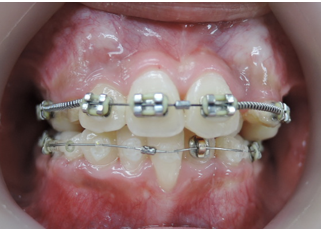

当院ではマルチループ(MEAW法)という上の写真で装着しているようなクネクネ曲がったワイヤーを使用して、上下の隙間を埋めていくことで歯並びを整えます。

歯並びが悪いだけでなく、困ったことに犬歯から奥歯にかけて歯が嚙み合っていない開咬の状態です。

一般的な矯正の治療法では中心から4番目の歯を抜いて隙間をつくり、飛び出した犬歯を並べて治療します。

しかし、この矯正方法は歯を横に動かす治療法なので、噛んだときにできる奥歯の上下の隙間を治すのが苦手です。